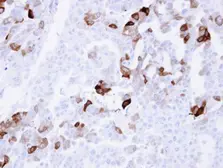

Images